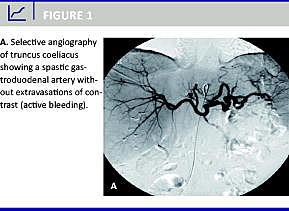

Intraarteriel embolisering synes at være en effektiv minimalt invasiv interventionsradiologisk metode til behandling af øvre nonvarikøse gastrointestinale blødninger, også i de tilfælde hvor aktuel blødning ikke kan påvises ved angiografi (Figur 1 ). Metoden er dog også forbundet med relativt mange tidlige reblødninger, og patienterne har relativt høj mortalitet både relateret til gastrointestinale blødninger og af andre årsager. Intraarteriel embolisering er desuden en effektiv metode til behandling af reblødninger.